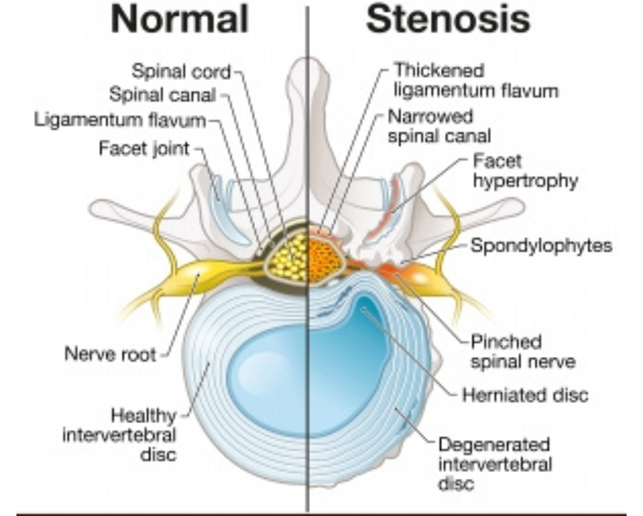

The structure of spine mainly responsible for spinal stenosis are ligamentum flavum and enlarged bone of facet joint and lamina. Spine stenosis occurs due to age related wear and tear of the spine. Ligamentum flavum gets calcified and facet joint gets arthritic. Therefore stenosis is a disease of elderly population around 55-60 years of age. Lifestyle factors like prolonged sitting or travelling, obesity, improper posture, sedentary lifestyle etc. can accelerate the wear and tear causing spinal stenosis to manifest at a younger age, say in 30’s and 40’s.

The problem causing structure in spinal stenosis that compress the thecae sac or nerve roots are mainly hypertrophied ligamentum flavum and enlarged bone (of facet joint or lamina). An ideal surgery for spinal stenosis should: